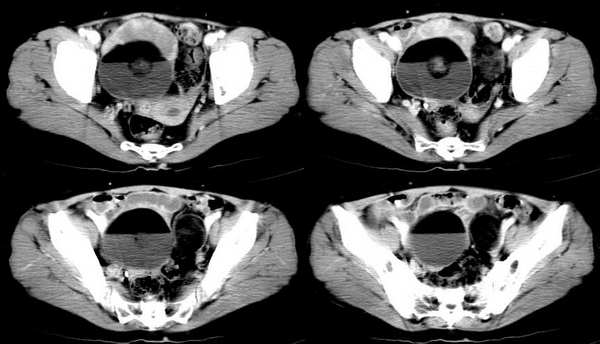

女,55岁,因下腹胀痛2月,b超发现盆腔包块7天,而入院,检查:右侧附件如女拳头大小包块,活动差,轻压痛,质中,子宫稍正常缩小,彩超示子宫4.9cmx2.6cmx2.3cm ,右侧附件包块示:8.7cmx9.1cmx6.3cm 的混合性回声,脂质分层征

双侧卵巢畸胎瘤,右侧为著

畸胎瘤(两侧)

双侧卵巢畸胎瘤

双侧畸胎瘤?????????!!!!!!!!!

难道我们看见脂肪密度就要诊断畸胎瘤吗?

同意大家畸胎瘤的诊断,但不能排除恶变的可能.

右侧肿块前壁的带状软组织密度影我认为是肠管所致,该部位的小肠肠襻由于受到肿瘤的推移呈水平样排列,这样在ct扫描时相邻的肠壁在某些层面上可以呈现宽带状软组织密度影。